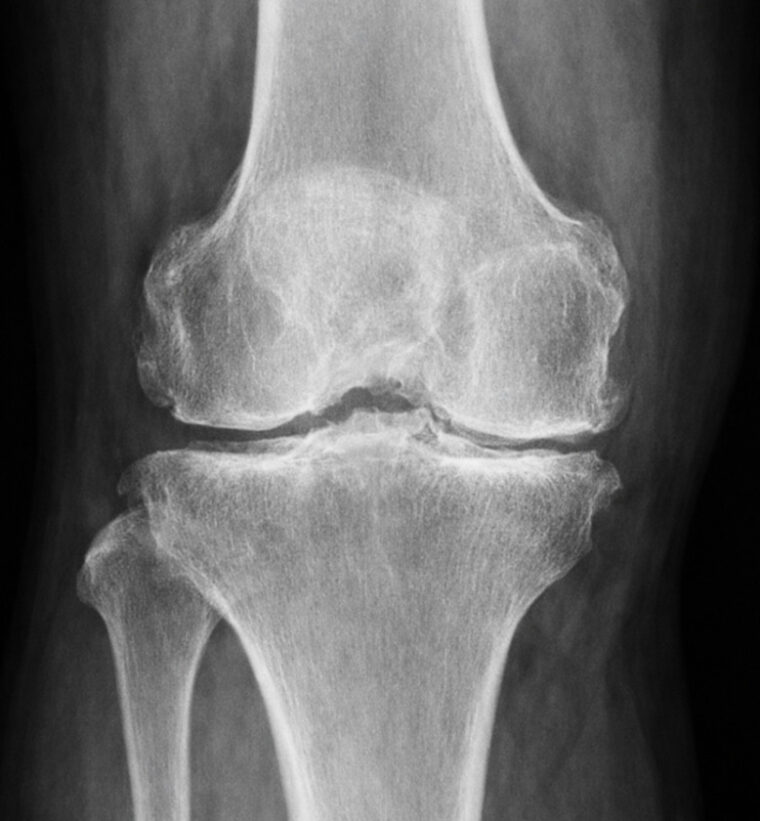

病院のレントゲンで変形性膝関節症は、

①関節のすき間が狭くなる

→ 軟骨がすり減っているサイン

②骨のトゲ(骨棘)ができる

→ 関節の変形が進んでいる状態

③骨が白く硬く見える(骨硬化)

→ 負担がかかり続けた結果

レントゲンでは軟骨自体は写りませんが、「骨と骨の間のすき間」 で軟骨の減り具合を判断します

また、関節の隙間の狭小化や骨の変形が確認できれば、変形性膝関節症の診断の大きな手がかりになります。

実は変形性膝関節症の初期は変化がわかりにくいです。

進行するとO脚変形や明らかなすき間の減少が見られるようになり ます。